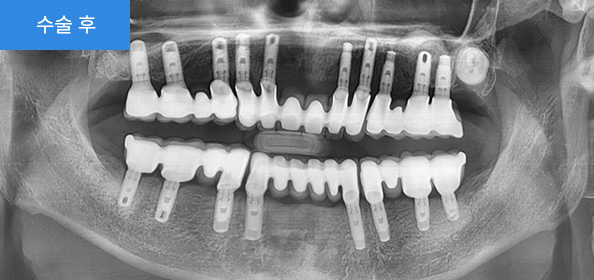

2020.12

투시장비 ‘아이스코프’를 사용하여 안전하게 임플란트 시술을 진행하였습니다. 어금니가 복원이 되면서 음식을 씹는 기능을 회복하였습니다.